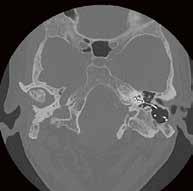

durch AiCE/ Volumendatensatz akquirieren beim Felsenbein-CT und -CCT.

Durch die Einführung des neuen Canon CT Aquillion One Genesis im Institut für Diagnostische und Interventionelle Neuroradiologie an der Medizinischen Hochschule Hannover (MHH) ist es nun möglich, mittels Volumenscan Körperbereiche von bis zu 16 cm Scanlänge in einer Rotation zu akquirieren. Dies brachte nicht nur deutliche Vorteile in der Ganzhirnperfusion bei der akuten Schlaganfallversorgung, sondern auch eine erhebliche Reduktion von Bewegungsartefakten durch die minimalste Scanzeit von 0,275 Sekunden!

Mit dem Volumenscan besteht nun die Möglichkeit, einen Bereich von 16 cm Länge mittels einer Röhrenrotation darzustellen. Dieser Bereich ist individuell anpassbar in 2-cm-Schritten, womit befundorientiert unter Beachtung des Strahlenschutzes der Untersuchungsbereich eingegrenzt werden kann. Die Untersuchungszeit ist gleichbleibend niedrig, unabhängig von der gewählten Scanlänge (2–16 cm).

Die HNO-Klinik der Medizinischen Hochschule Hannover setzt ca. 500 Cochlea-Implantate ein, womit sie aktuell weltweit den Spitzenreiter darstellt. Für die OP-Planung ist eine sehr gute örtliche Auflösung und ein starker Kontrast des Felsenbeins erforderlich, um dem Operateur, der die Elektrode in die Schnecke das Runde Fenster zielgenau einführen muss, eine gute Planungsgrundlage zu schaffen. Auch muss post die intracochleare Lage kon werden, was technisch eine große Herausforderung darstellt, da die Strukturen in diesem Areal sehr fein sind und durch das implantierte Metall Aufhärtungsartefakte ent die Diagnostik dadurch erschweren.

Goldstandard war bis dato das DVT, das durch die Cone Beam Technik stark reduzierte Aufhärtungsartefakte aufwies und somit genaue Aussagen zwecks Lagekontrolle liefern konnte. Es kommt jedoch für einen Großteil der Patienten (Kinder 1–5) aufgrund der vorher erwähnten Gründe nicht in Frage. Ein großer Vorteil des neuen Canon CTs ist die bereits gut etablierte Metallartefakt-Reduktion SEMAR,die durch Algorithmen die Artefakte stark reduzieren kann. Es entsteht dadurch

keine wesentliche Einschränkung zur Identifizierung der ersten Kontaktelektrode im Vergleich zum DVT.

Auch der neuentwickelte Deep Learning Algorithmus AiCE des Canon Aquilion ermöglicht die Reduktion der Dosis, bei gleichbleibendem bzw. verbessertem Bildeindruck. AiCE bietet zudem eine scharfe Abgrenzung feiner Strukturen und reduziert das durch Low-DoseTechnik auftretende Rauschen. //

2. Vergleich eines cranialen CTs mit und ohne Deep Learning Rekonstruktion AiCE:

CTDI

30,2 mGy 544,6 mGy*cm

Felsenbein-CT Felsenbein CT-Rekonstruktion

DVT: CDTI DLP Volumen-CT 6,5 mGy 39 mGy*cm DVT 7,3 mGy 76,6 mGy*cm Vorgänger-CT 17,1 mGy 176 mGy*cm CT vs. DVT

„AiCE unterstützt die Diagnosefindung in der Neuroradiologie dank der sofort sichtbar besseren Bildqualität bei gleicher Dosis.“